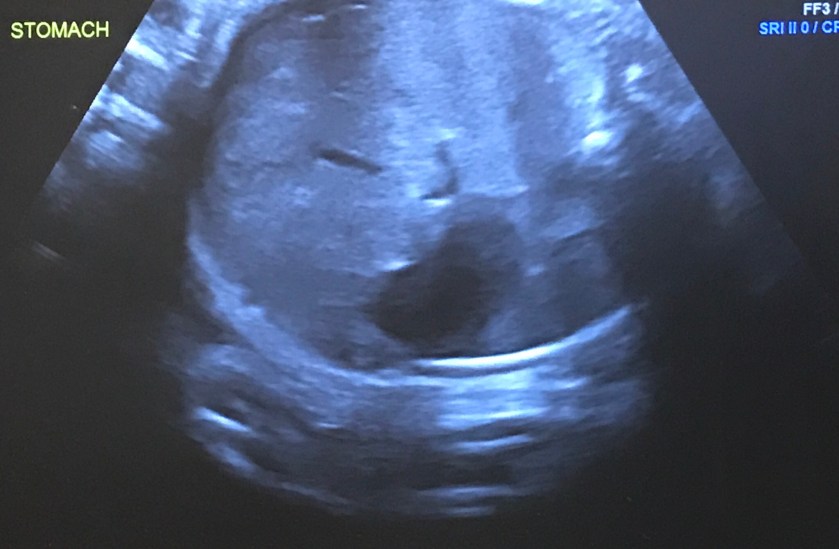

My second appointment of the week was for my 36 week growth scan. The technician worked quickly. At this stage the baby’s organs are hard for most nonmedical professionals to determine what they are, like the stomach below. The baby our his or her hands up over their face so we were not able to get a good 3D shot.